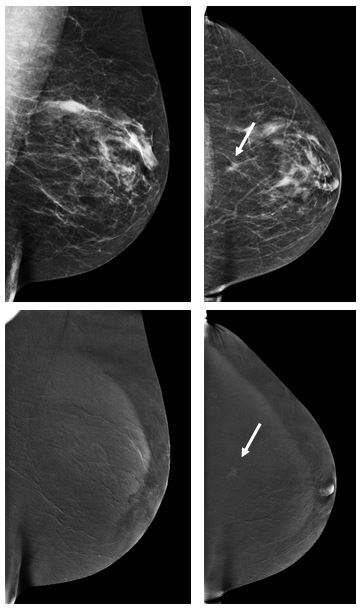

Contrast–enhanced mammography: Is a single view enough?

Contrast-enhanced mammography is developing as an alternative to MRI in some situations. However, in order to decrease the radiation dose, the question is if we can perform only a single view instead of a double view. From this cohort, the answer is not positive.

Article: Evaluation of single-view contrast-enhanced mammography as novel reading strategy: a non-inferiority feasibility study